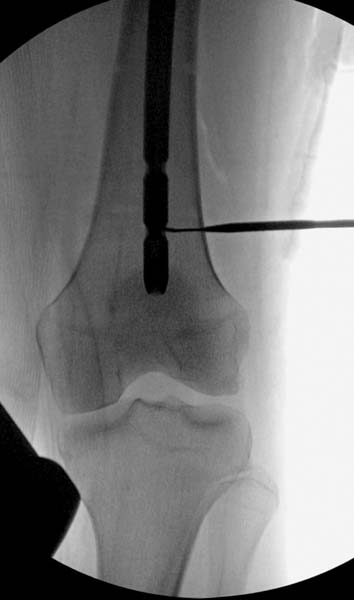

Остеосинтез бедра не стали делать из-за множественных переломов ребер с ушибом грудной клетки и поэтом у закончили фиксацию бедра наружным фиксатором.

Около 11.00 вечера больная переведена в реанимацию, без сознания, но стабильная.. На третьий день провели стабилизацию перелома бедра антеградным остеосинтезом.

Закрытый БИОС решает множественные проблемы связанные с лечением переломов, но проблема дистальной блокировки без рентгена до сих пор остается нерешенной. Рекламированные производителями приспособления для дистальной блокировки из-за различной кривизны кости не эффективны или стоит очень дорого (Smith&Nephew SureLock). Задержка операции из-за блокировки не всегда удовлетворяет, и многих вынуждает искать альтернативные методы фиксации. С результатами таких действий, остеомиелитом и несращениями, встречаемся в ежедневной жизни..

Для решения проблемы дистальной блокировки компания DigiMed недавно предложила систему блокировки без рентгена. Пока в стране только два набора и только для антеградных гвоздей, но компания работает над созданием устроиства для других гвоздей тоже..

Результат первых случаев показала отсутствие разницы между занятиями на муляжах, а также Workshop и с удивительной точностью вывел латерально над кожей специальное сверло. Дальше по сверлу тонкий направитель и проводится сверление каннюлированным сверлом....